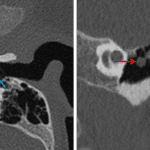

Age: 2

Sex: Male

Indication: Left-sided conductive hearing loss

Congenital cholesteatoma